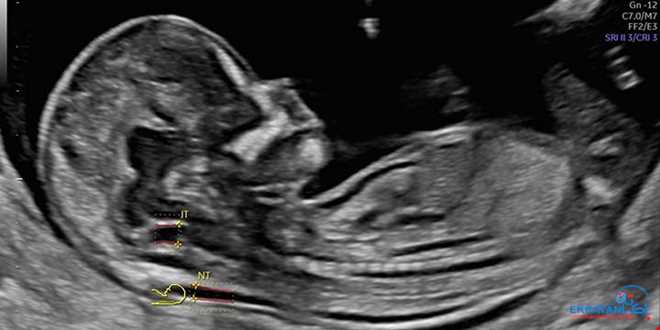

غربالگری NT یا Nuchal Translucency یک سونوگرافی تخصصی دوران بارداری است که با اندازه‌گیری ضخامت مایع پشت گردن جنین در سه‌ماهه اول، به تشخیص زودهنگام برخی ناهنجاری‌های کروموزومی مانند سندرم داون (تریزومی ۲۱)، تریزومی ۱۸ و تریزومی ۱۳ کمک می‌کند. این بررسی معمولا با ارزیابی ساختارهای اولیه جنین و برخی مارکرهای دیگر همراه است.

بهترین بازه زمانی انجام تست NT از هفته ۱۱ تا پایان هفته ۱۳ بارداری (ترجیحاً بین ۱۱ هفته و ۰ روز تا ۱۳ هفته و ۶ روز) است. انجام این سونوگرافی خارج از این محدوده، دقت تشخیص را کاهش می‌دهد، زیرا بعد از این سن، تغییرات فیزیولوژیک جنین باعث غیرقابل اعتماد بودن اندازه‌گیری می‌شود.